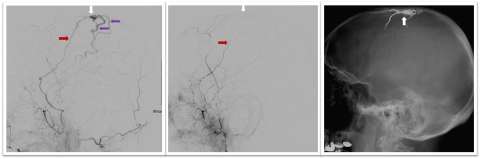

- Endovascular liquid embolization: This minimally invasive technique is performed by inserting a catheter through the groin (or other vessel), then injecting a liquid that solidifies in the blood vessel and cuts off blood flow to the fistula. The cerebrovascular team at UCLA is actively involved in research and testing of new liquid embolic treatments (Figures 1-2). This is the most common method of treating DAVF, and it is often curative.

- Coil embolization: Micro-coils made of platinum are placed into the artery, vein or venous sinus to seal off the DAVF abnormal connection and prevent blood flow through it.